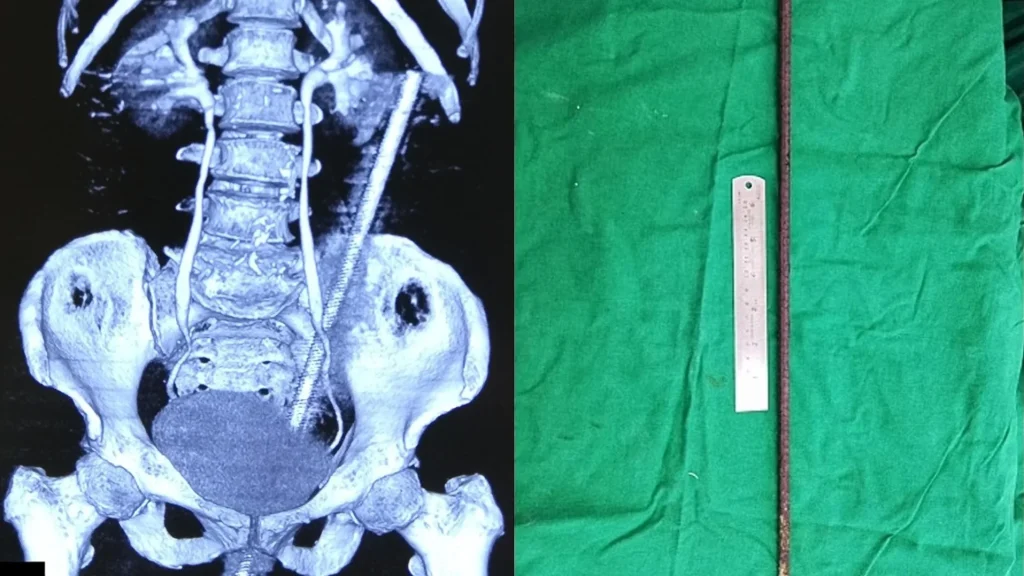

Η γυναίκα βρισκόταν στο χωράφι που βρίσκεται δίπλα στο σπίτι της, φροντίζοντας τις αγελάδες της, όταν η μοίρα της έπαιξε ένα τρομακτικό παιχνίδι. Μία σκουριασμένη μεταλλική βέργα, μήκους σχεδόν 60 εκατοστών, είχε τοποθετεί στο έδαφος του χωραφιού, προκειμένου να στηρίξει αναρριχώμενα φυτά. Η γυναίκα, ενώ φρόντιζε τις αγελάδες της, έχασε την ισορροπία της λόγω της «ανησυχίας» μιας αγελάδας, καθώς ήταν δεμένη μαζί της με ένα σχοινί στον καρπό της, και κάθισε επάνω στη βέργα, με αποτέλεσμα να εισέλθει από τον πρωκτό της, να διαπεράσει το έντερό της και να επεκταθεί πίσω από την κοιλιακή κοιλότητα.

Η κατάσταση της γυναίκας ήταν σοβαρή, καθώς η βέργα είχε προκαλέσει διάτρηση του εντέρου και είχε εισχωρήσει στον χώρο πίσω από την κοιλιακή κοιλότητα. Παρά τη σοβαρότητα του ατυχήματος, η βέργα δεν κατάφερε να προκαλέσει βλάβες σε αιμοφόρα αγγεία και ζωτικά όργανα, κάτι που αναφέρθηκε στην ιατρική έκθεση για την περίπτωση της.

Η χειρουργική επέμβαση, που διήρκεσε δύο ώρες, περιλάμβανε την αφαίρεση της ράβδου μέσω του πρωκτού και την αποκατάσταση της διάτρησης. Μετά την επέμβαση, η γυναίκα είχε ναυτία και κοιλιακούς πόνους ενώ δεν μπορούσε να περπατήσει. Ωστόσο, η ανάρρωσή της προχώρησε χωρίς προβλήματα και, μετά από περίπου δέκα ημέρες, κατάφερε να επιστρέψει στο σπίτι της.